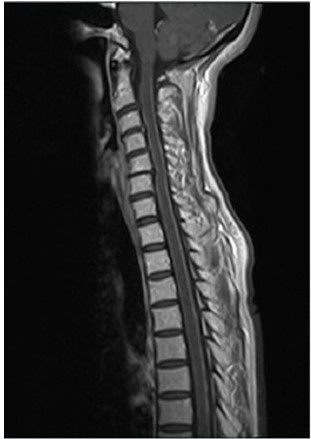

Mujer de 53 años de Lima, Perú sin antecedentes patológicos de importancia, acude al hospital por presentar disminución de fuerza muscular en miembros inferiores, parestesia y dolor neuropático 2 meses antes del ingreso y que progresó hasta necesitar una silla de ruedas 5 semanas antes de ser admitida por incapacidad de permanecer en bipedestación. La paciente reportó tos seca no productiva 3 semanas antes del ingreso asociado a una pérdida de peso de 5 kg en 2 meses. Negó fiebre, diplopía, cefalea. Su historia clínica era significativa por ser no fumadora y recibir 2 dosis de vacuna COVID-19 Sinopharm®. Antes de ser admitida, se realiza una resonancia magnética cerebral (RMN) y de columna donde se evidencia realce leptomeníngeo desde la unión bulbomedular hasta el conus medularis (Figura 1).